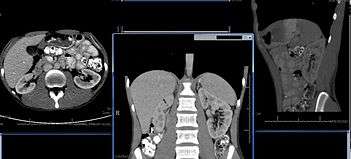

Imaging

Imaging studies are important in the evaluation of structural renal disease caused by urinary tract obstruction, renal stones, renal cyst, mass lesions, renal vascular disease, and vesicoureteral reflux.[20]

Imaging techniques used most frequently include renal ultrasound and helical CT scan. Patients with suspected vesicoureteral reflux may undergo voiding cystourethrogram (VCUG).